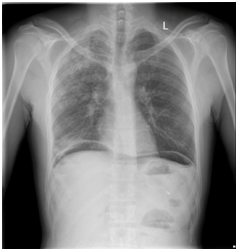

X-ray erect abdomen and chest x ray revealed air under diaphragm (Figure1-2) .He underwent lab tests , which showed normal total leukocyte count (8.67x10^3/µl), nevertheless his coagulation profile (prothrombin time: 20.2 INR: 1.85) was deranged suggestive of sepsis, peritoneal fluid(intraoperative) sent for culture and sensitivity was sterile.

Figure 2 X ray Chest PA view.